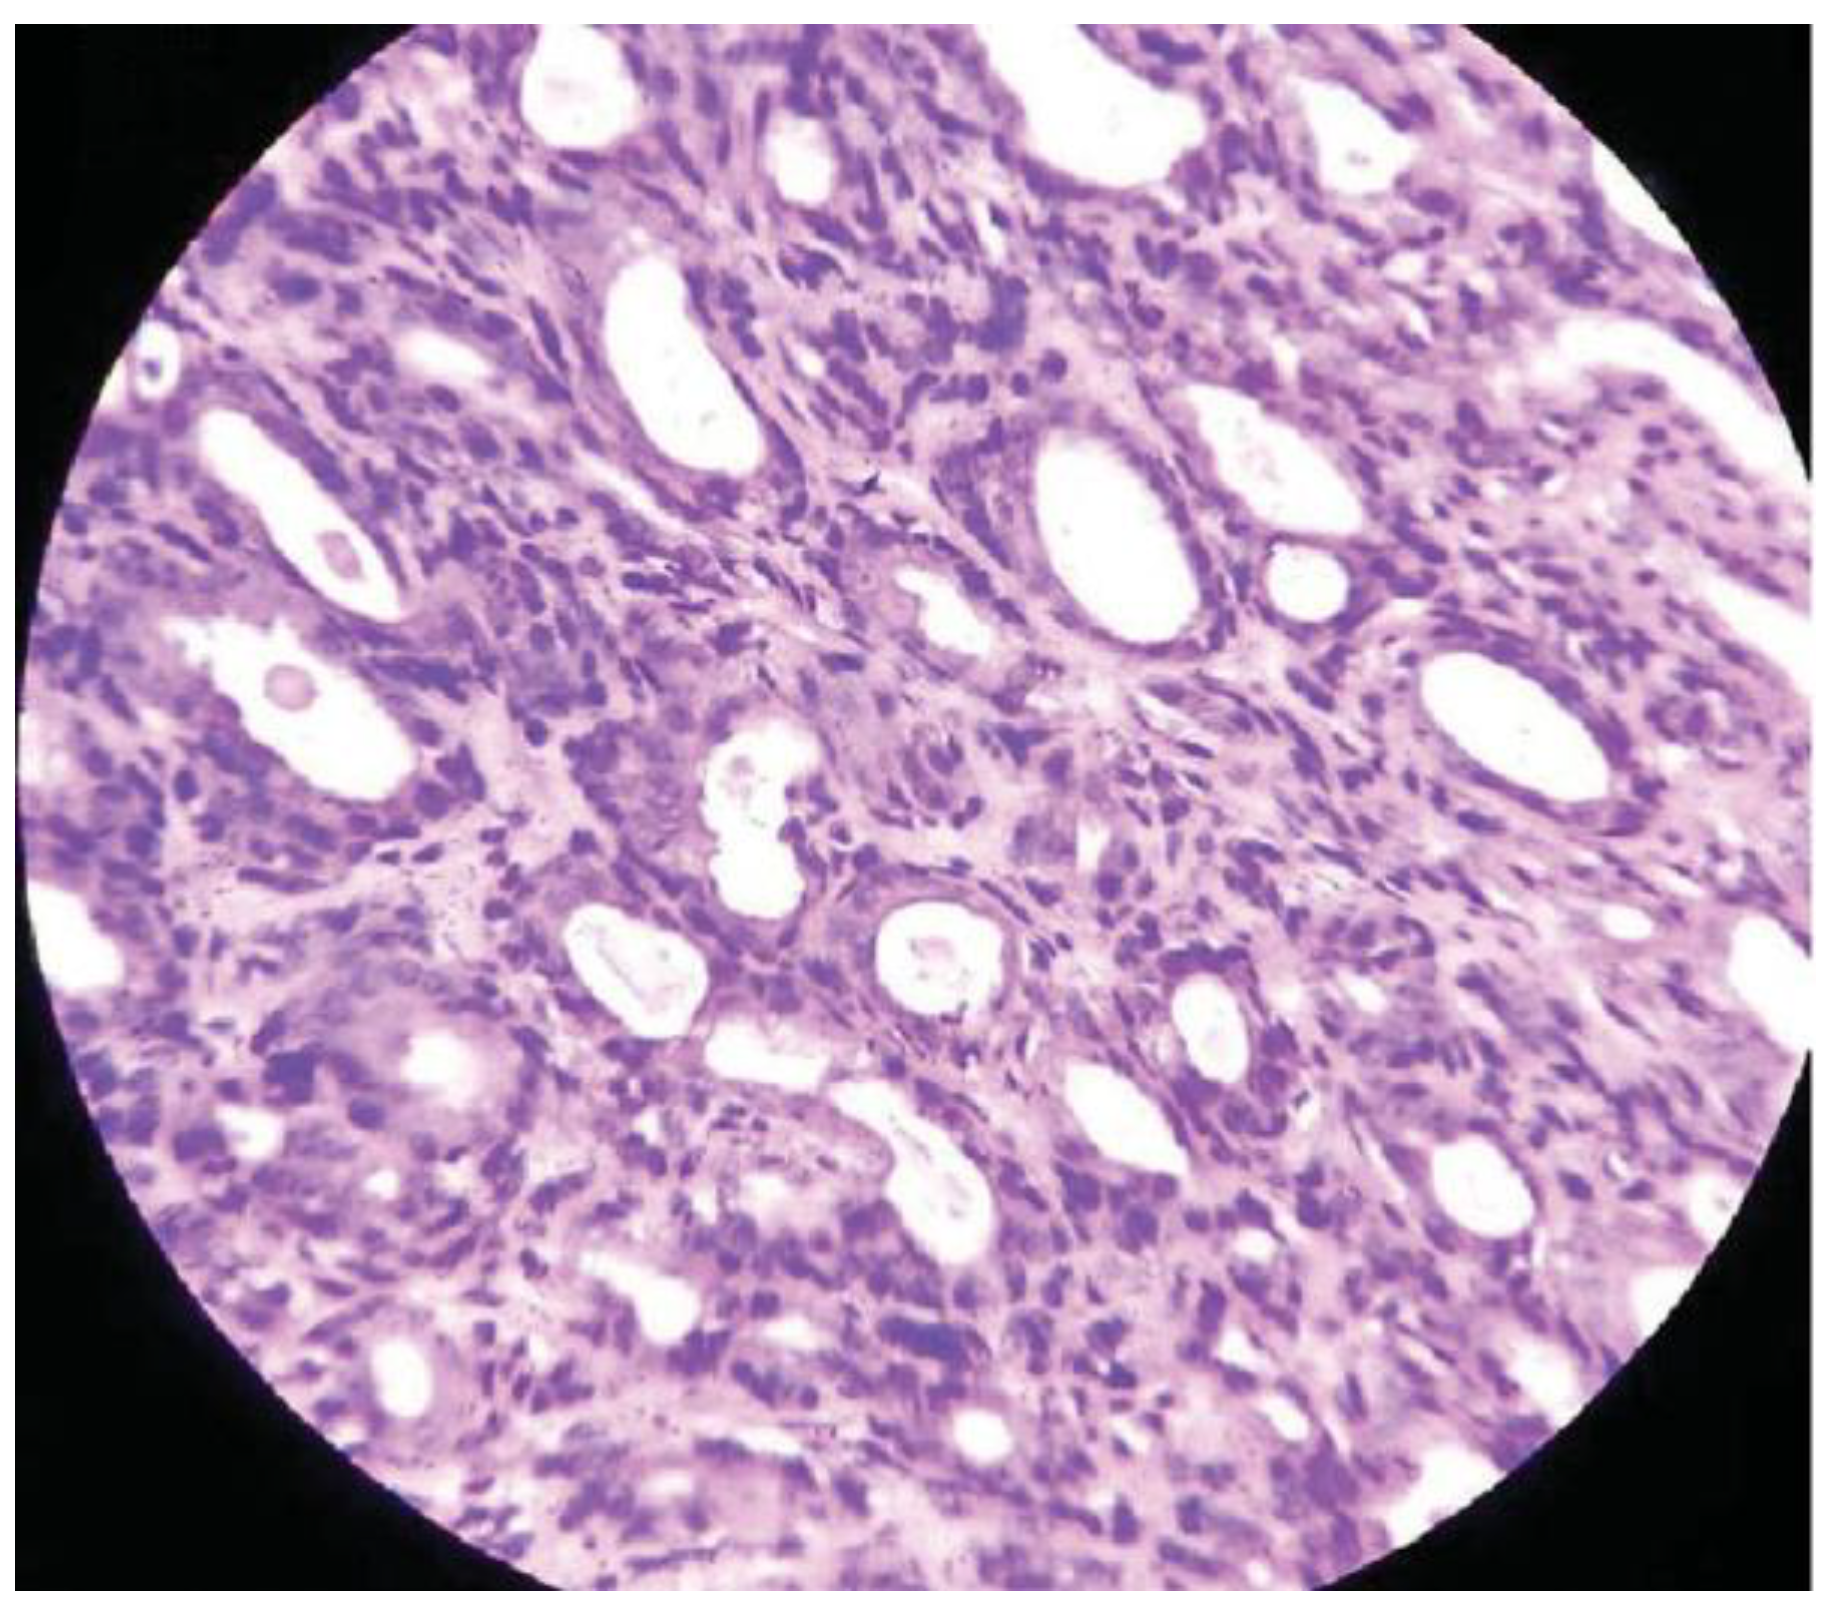

:Case Presentation

Discussion